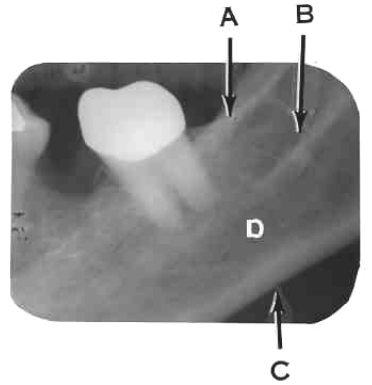

30. What is shown by arrow C?

31. What arrow shows?

32. What is showing by the arrow?